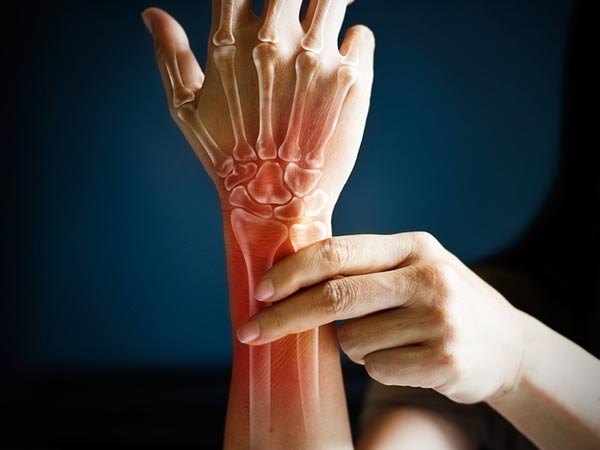

टखने और कलाई को भी कर सकता है प्रभावित

यह स्थिति अक्सर कंधे को ज्यादा प्रभावित करती है। कैल्शियम ज्यादात्तर रोटेटर कफ (कंधों के जोड़ के पास मौजूद मांसपेशियों और नसों का समूह ) के चारों ओर जमा होता है। इस स्थिति के वजह से आपके ऊपरी बांह की हड्डी, कंधे के सॉकेट के भीतर से लॉक हो जाती है। इसके आपके टखने, घुटने, नितंबों, कलाई और एड़ियों को भी प्रभावित करता है।

ब्लड टेस्ट और एक्स-रे की मदद से इसका पता लगाया जाता है। इलाज के लिए सूजन दूर करने वाली दवाएं और आइस थैरेपी की जाती है। कैल्शियम के कारण डैमेज अधिक होने पर सर्जरी की जाती है।